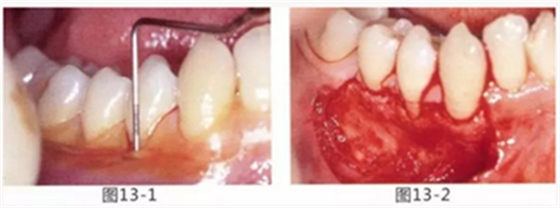

由于口腔前庭較淺且沒有附著齦,使菌斑容易滯留且刷牙困難的病例

圖13-1 使用碘溶液進行染色,頰側(cè)基本看不到角化牙齦,且無口腔前庭的狀態(tài)。

圖13-2 為了擴張口腔前庭,獲取附著齦而進行了游離齦移植術(shù)。受皮床一定不能發(fā)生移動,盡可能使厚度均等。

圖13-3 手術(shù)剛結(jié)束的狀態(tài)。通過骨膜縫合的褥式縫合將移植片固定,使其無法移動。

圖13-4 手術(shù)完成2年后的狀態(tài)??谇磺巴サ玫綌U張,即使正在進行正畸治療,也沒有妨礙到清潔。